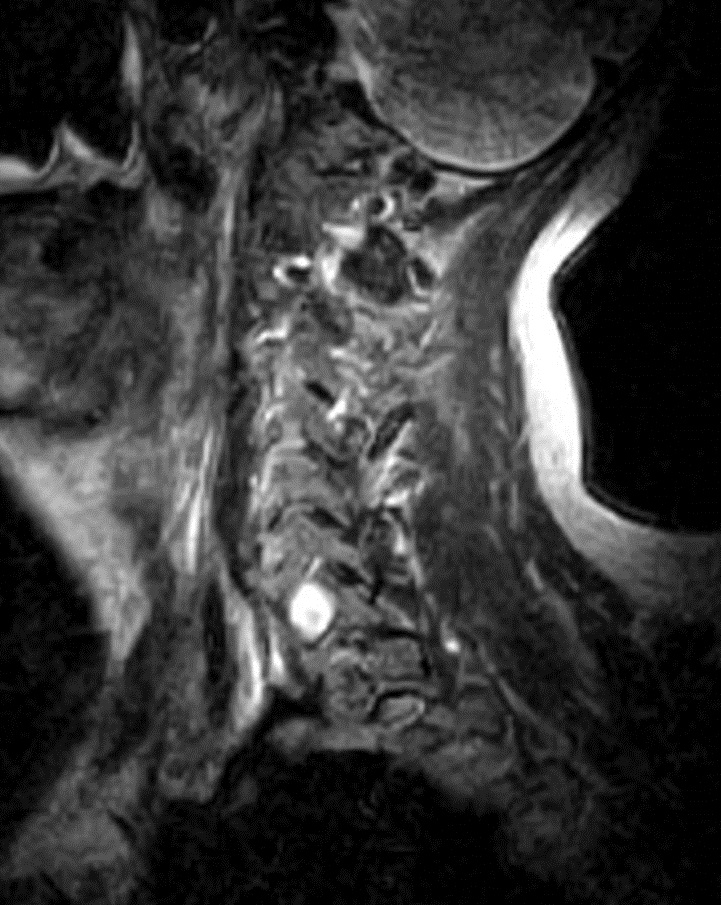

I have provided some select images from the MRI study that was obtained. Initially, the study was ordered non-contrast. Fig. 1 is a midline T-2 weighted image. It demonstrates a degree of posterior disc bulging at C6-C7. No focal posterior discal prominence was noted that would indicate a herniation. Fig. 2 is a gradient echo weighted image through the C6-C7 disc space. In this image, there is obvious expansion of the left intervertebral foramen with a degree of erosion of the facet at the posterior margin of the foramen. The signal intensity is bright on this image, compared to the normal intermediate signal intensity noted within the right foramen. You will note a degree of irregularity at the posterior margin of the disc in this cut, consistent with the disc bulging seen on the sagittal images. There is not sufficient encroachment of the central canal however to account for a neurologic deficit. A left parasagittal STIR image (Fig.3) reveals an obvious focus of abnormal signal within the left C6-C7 IVF that corresponds to the finding that was noted on the axial image. The signal intensity of this area was high on the STIR, gradient echo, and T-2 weighted images, and low on the T1 weighted images, consistent with fluid. At this point what diagnoses would you entertain, and would you order any follow-up imaging or testing?

The fluid characteristics of this lesion may be consistent with two probable considerations. It is possible that there is dilation of the dural root sleeve and that the signal represents cerebrospinal fluid. This condition is not neoplastic, but rather developmental, and does not constitute a major health concern. Another possibility is that the lesion does represent a neoplastic process. Both conditions may look similar on MRI. A rather simple way to distinguish between the two would be to perform a follow-up MRI examination with the administration of intravenous contrast (gadolinium). If the mass is neoplastic there would be expected enhancement of the mass, the signal would become brighter on the T-1 weighted postcontrast images. If the mass simply represents a fluid filled sac, such as dural root sleeve dilation or cyst, there will be no enhancement of the mass.